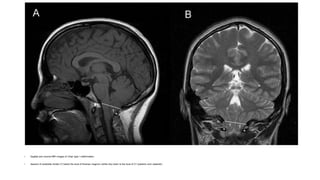

• Sagittal and coronal MRI images of Chiari type I malformation.

• descent of cerebellar tonsils (T) below the level of foramen magnum (white line) down to the level of C1 posterior arch (asterisk).

• Sagittal andcoronal MRI images of Chiari type I malformation. • descent of cerebellar tonsils (T) below the level of foramen magnum (white line) down to the level of C1 posterior arch (asterisk).

Chiari malformation

• The brainstem and cerebellum are elongated downward into the

cervical canal - pressure on both the caudal midline cerebellum and

the cervicomedullary junction.

• Spontaneous or positional downbeat nystagmus

• central nystagmus can also occur.

• #38 MRI is the procedure of choice for identifying Chiari malformations; midline sagittal sections clearly show the level of the cerebellar tonsils.